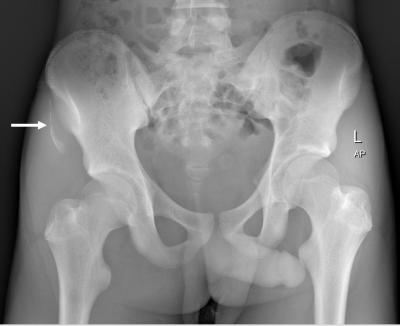

Figure 1: Plain pelvis radiograph showing avulsion fracture of right anterior superior iliac spine (white arrow).